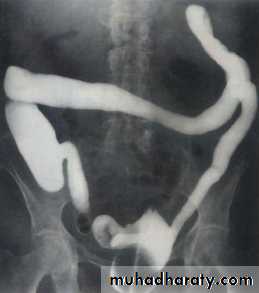

Crohn disease

• Crohn disease is characterized by transmural granulomatous inflammation with deep ulceration, sinuses and fistula tracts.

• Crohn disease may involve any part of the gastrointestinal tract from mouth to anus with small bowel involvement alone in 30 %, large bowel in 30 % and both small and large bowel in 40 %.

• it nearly always affect the terminal ileum.

• Involvement is discontinuous with normal bowel between diseased segments (‘skip lesions’).

Signs of Crohn disease on barium studies include:

• Ulcers (rose-thorn ulcers or deep fissures).

• Strictures (string sign).• Intestinal obstruction.

• ‘Cobblestoning’ due to fissures separating islands of intact mucosa

• Segmental distribution: diseased segments separated by normal bowel

• Separation of loops of bowel due to bowel wall thickening or an inflammatory mass

• When involved the cecum is usually contracted.

• The rectum is often spared

• Ileocecal valve is normal or narrowed; terminal ileum stenosed.

• Fistula to other loops of small bowel, colon, bladder or vagina